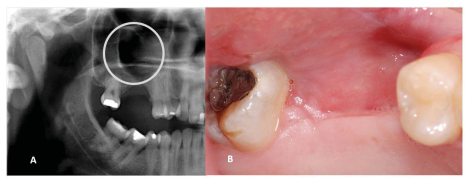

A 33-year-old man reported an episode of bleeding in the mouth and extravasation of fluid through the nose during liquid ingestion. The bleeding occurred in the upper right first molar region over one year, and there was extravasation of blood and serous fluid through the nose associated with pain and pressure on the same side of the face, when the patient was yawning. The medical condition did not show any comorbidity. In the intraoral exam, a 7mm periodontal pocket was detected. A gingival recession was also observed around the UFM and a Valsalva test was negative. The panoramic x-ray showed vertical bone loss in the super right first and second molar (URFSM) region. There was a bilateral alveolar ex-tension of maxillary sinus with opacification on the right maxillary sinus only (figure 2). We prescribed a CBCT exam, which showed severe furcation in-jury, external root reabsorption and vertical bone loss around cortical floor, and a thickening of the sinus mucosa around the URFSM. There was a rupture in the floor of the cortical sinus (figure 3). The diagnostic hypothesis was OMS related to periodontal disease or maxillary sinus tumor of the maxillary sinus floor. The extraction of the URFSM was done with curettage of the soft tissue associated with dental roots. In the surgical procedure, a 1cm diameter oroantral communication was observed, treated with intra alveolar fibrin sponge covered with a vestibular flap of oral mucosa (figure 4). The microscopic analysis showed no signs of malignancy and chronic inflammatory cell infiltrate compatible with inflammatory periodontal disease (figure 5). The final diagnosis was odontogenic maxillary sinusitis related to periodontal disease. A corticosteroid nasal spray was prescribed, and three months after the surgical procedure no clinical signs or symptoms were observed. A new panoramic x-ray six months after the surgical procedure showed normal radiopacity of the right maxillary sinus (figure 6).